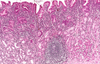

what is shown by the arrows in this pathology?

GERD

mucosal and submucosal lymphocytes, neutrophils, eosinophils